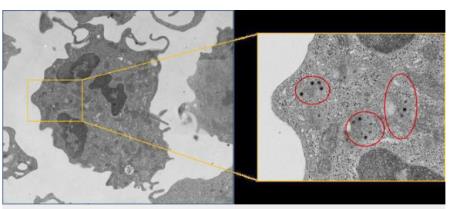

Các nhà khoa học Nga vừa phát minh một thiết bị chẩn đoán sớm ung thư và bệnh lao.